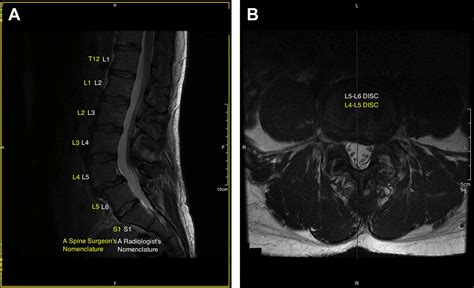

Accurate diagnosis of conditions affecting the lumbosacral transitional segment is essential for effective treatment. Several diagnostic methods are commonly used to evaluate this region:

• Imaging Studies: Imaging techniques such as X-rays, MRI, and CT scans are crucial for visualizing the anatomy of the lumbosacral region. These studies can reveal degenerative changes, herniated discs, spinal stenosis, and other abnormalities.

Advances in technology have significantly improved the diagnosis and treatment of conditions affecting the lumbosacral transitional segment. Imaging techniques, such as MRI and CT scans, provide detailed visualizations of the spine, allowing for accurate diagnosis and treatment planning. Surgical techniques, such as minimally invasive procedures, offer less invasive options for addressing structural issues in the spine.

Imaging techniques, such as MRI and CT scans, provide detailed visualizations of the spine, allowing for accurate diagnosis and treatment planning. These techniques can reveal degenerative changes, herniated discs, spinal stenosis, and other abnormalities. Surgical techniques, such as minimally invasive procedures, offer less invasive options for addressing structural issues in the spine. These procedures can reduce recovery time, minimize scarring, and improve outcomes.